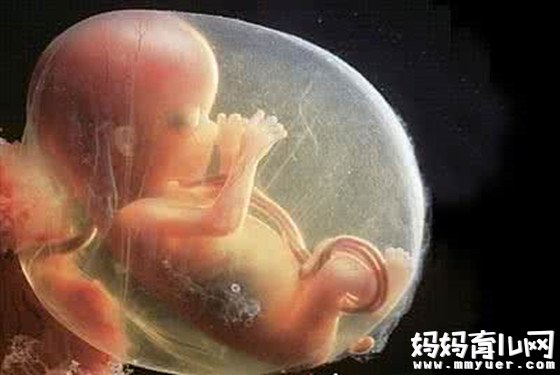

怀孕28周胎儿真实图片

28周的胎儿现在坐高约26厘米,身长约37.6厘米,体重超过900 克。

这周的胎儿可以睁开眼睛了!他的睫毛也已经完全长出来了,他的脂肪还在累积,为出生后在妈妈子宫外的生活做准备。

现在的宝宝几乎占满了整个子宫,随着空间越来越小,胎动也在减弱。但假如把手放在你的腹部,可以感觉到胎儿的活动。他可能会用小手、小脚在你的肚子里又踢又打,有时还会让自己翻个身,把你的肚子顶得一会儿这里鼓起来一会儿那里又鼓起来,也有的胎儿相对比较安静,胎儿的性格在此时已有所显现。